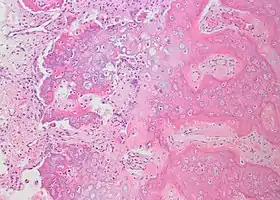

Histopathology

Bone Bizzare Parosteal Osteochondromatous Proliferation